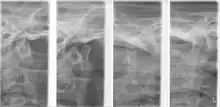

Plain radiography

This method of imaging allows the visualisation of the joint's mineralised areas, therefore excluding the cartilage and soft tissues.[49] A disadvantage of plain radiography is that images are prone to superimposition from surrounding anatomical structures, thereby complicating radiographic interpretation.[49] It was concluded that there is no evidence to support the use of plain radiography in the diagnosis of joint erosions and osteophytes.[50] It is reasonable to conclude that plain film can only be used to diagnose extensive lesions.[50]

Panoramic tomography

The distortion brought about by panoramic imaging decreases its overall reliability. Data concluded from a systematic review showed that only extensive erosions and large osteophytes can be detected by panoramic imaging.[50]